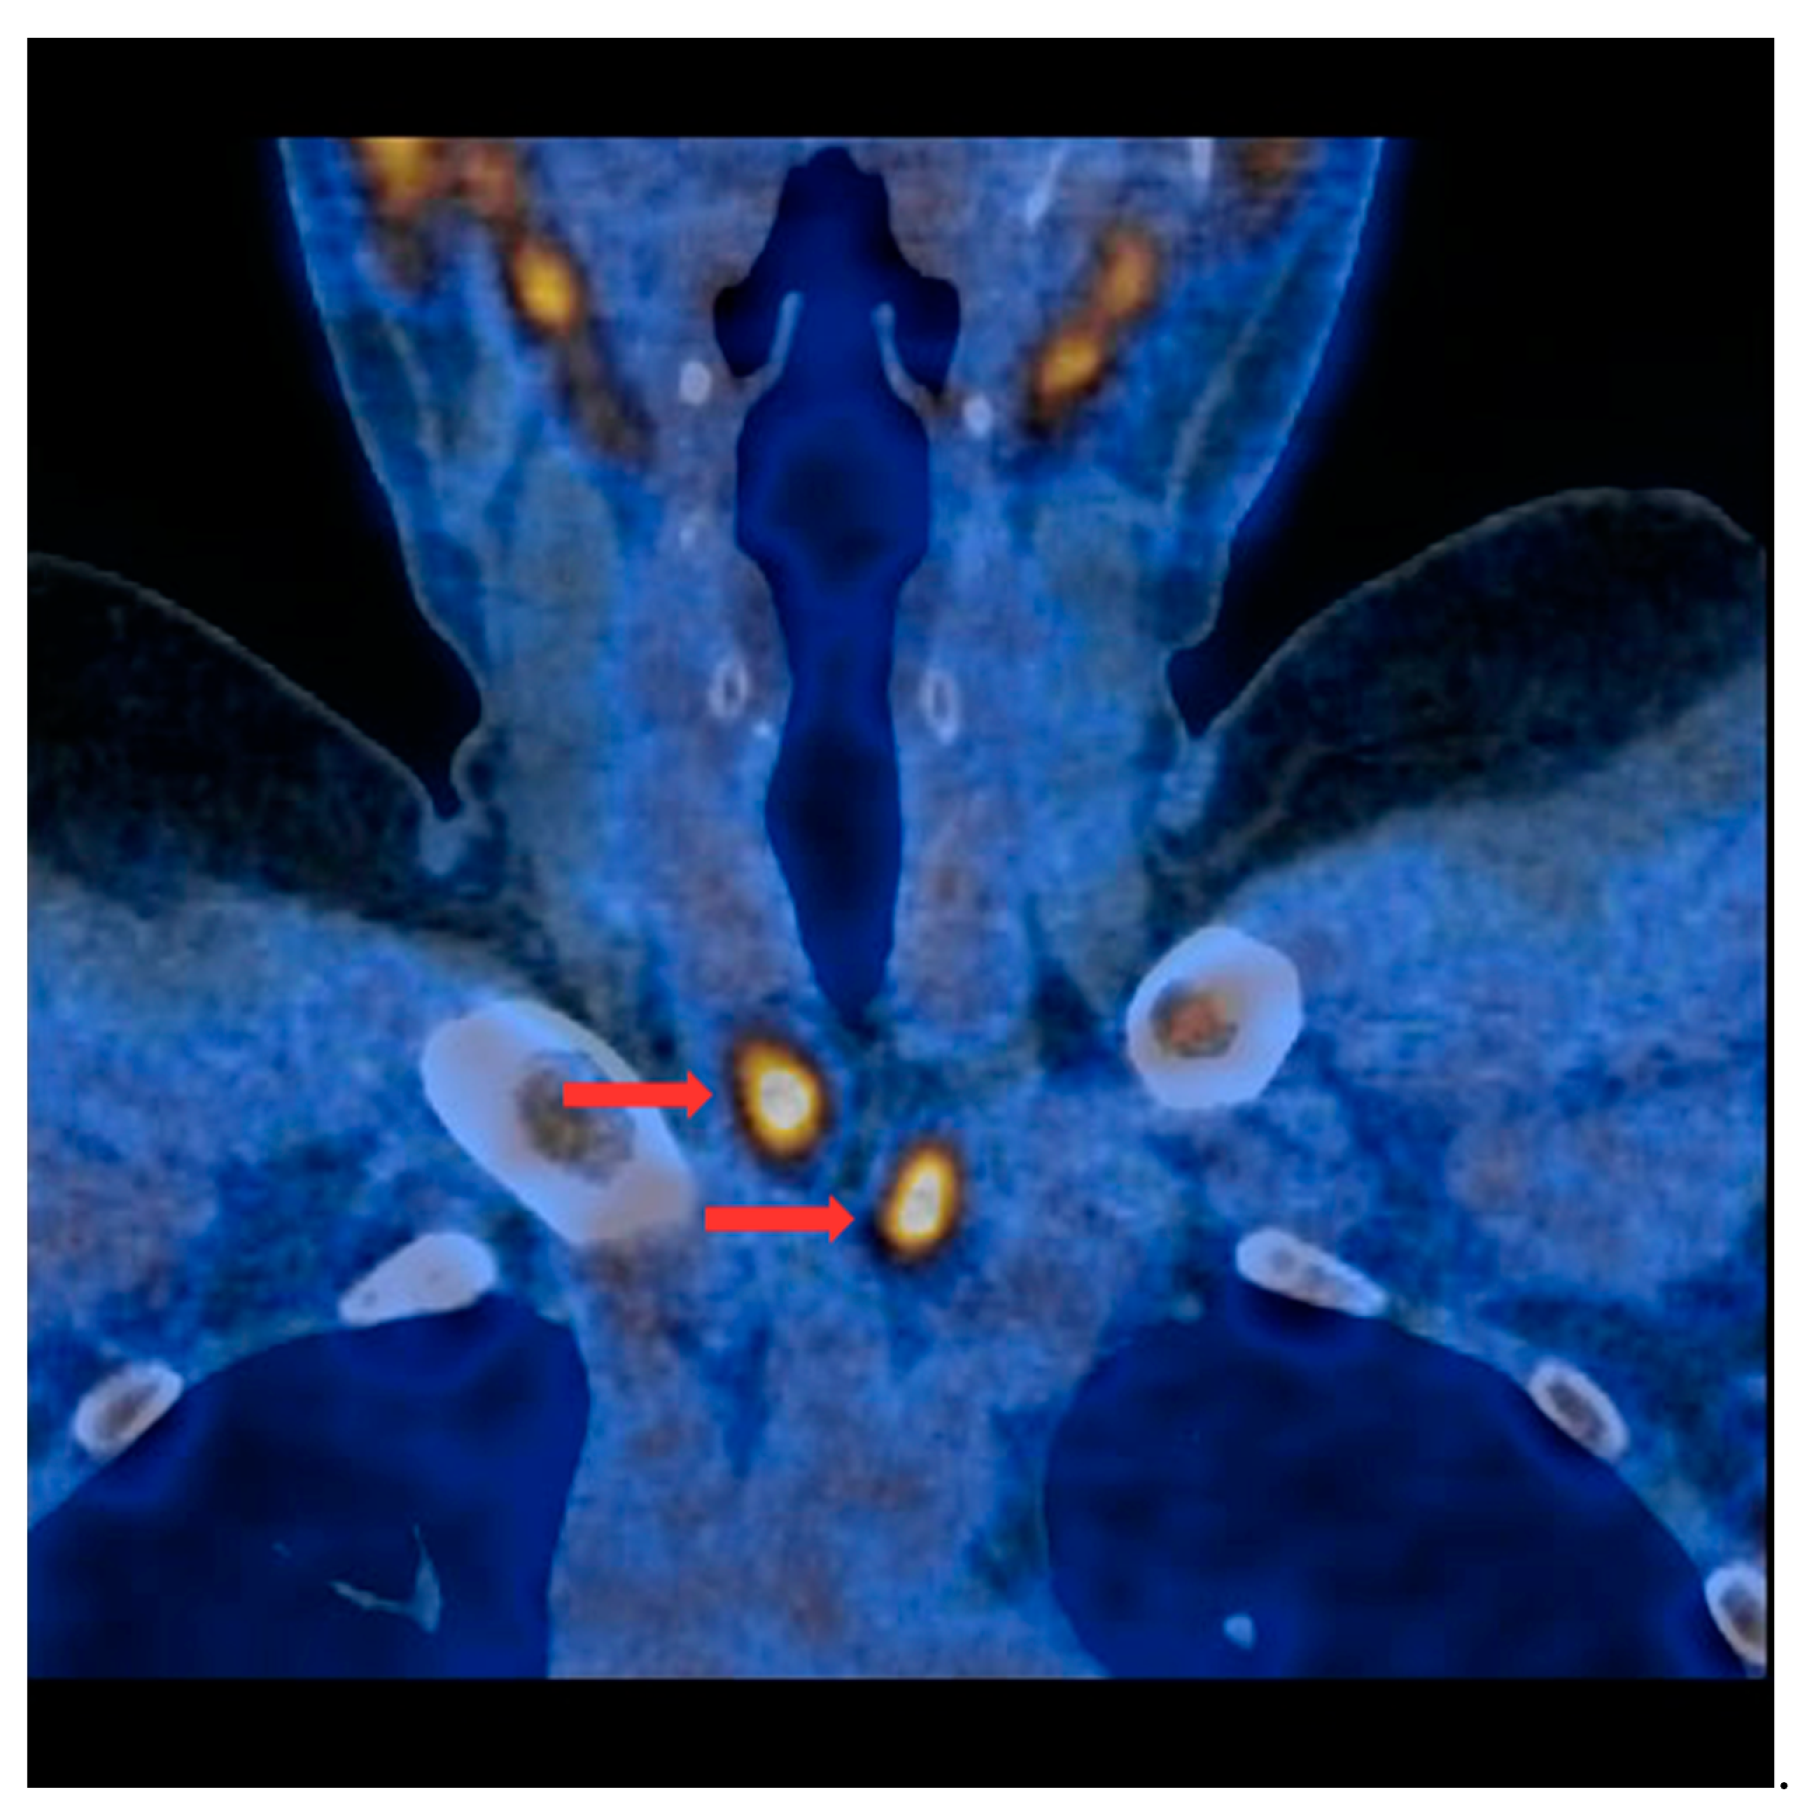

PET/CT with [11C]MET was performed on 19 patients, with negative results for both first-line imaging examinations. In this group, a positive result was obtained in 89.5% of the patients (17/19) (Figure 1 and Figure 2). In 2 patients (10.5%), the result was assessed as inconclusive (both of these patients showed accumulation of the radiotracer in a single lesion, the location and structure of which indicated that it might be a mediastinal lymph node; however, these lesions were not histologically verified due to revealed contraindications for surgery). Multiple lesions were observed in 57.9% of the patients (11/19) (Figure 3). Ectopic lesions were observed in 21.1% of the patients (4/19) (Figure 4). In total, 34 foci of increased accumulation of the radiotracer, considered as parathyroid glands, were observed. Additionally, in 15.8% of the patients (3/19), foci of increased accumulation of the radiotracer in the bones corresponding to brown tumors were observed (Figure 5a,b). Detailed results of the PET/CT examinations with [11C]MET are shown in Table 1.

Figure 3.

PET/CT with [11C]MET—frontal projection. Two visible foci of increased radiotracer accumulation (red arrows) corresponding to the parathyroid glands (multiple lesions) below both thyroid lobes.